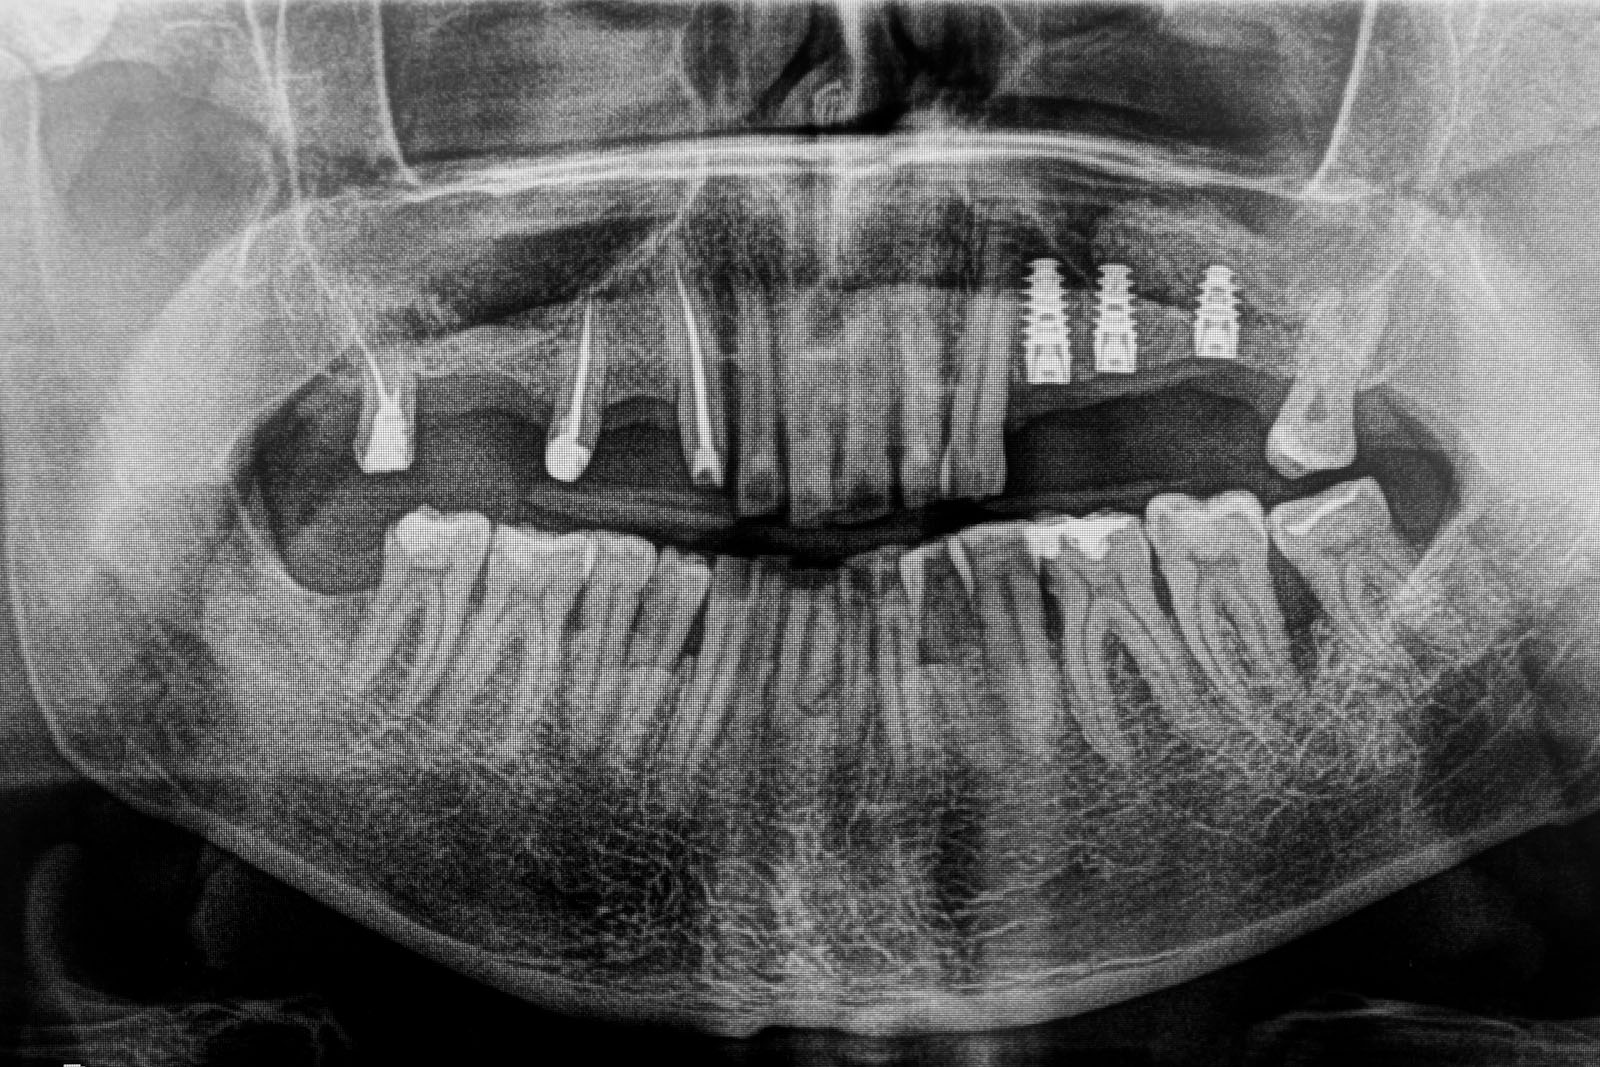

Przed podjęciem leczenia należy określić stopień zaniku kości szczęk oraz żuchwy. W tym celu przeprowadza się badanie kliniczne oraz odpowiednią diagnostykę obrazową pacjenta. Uwzględnia ona zdjęcie panoramiczne OPG jako podstawę dwuwymiarowego obrazowania podłoża kostnego oraz możliwe jest badanie tomograficzne CT lub bardziej precyzyjna tomografia stożkowa CBCT. Opcjonalnie wykorzystywana diagnostycznie tomografia pozwala na bardziej wnikliwą ocenę stopnia zaniku kości w trójwymiarowym, przestrzennym obrazie.